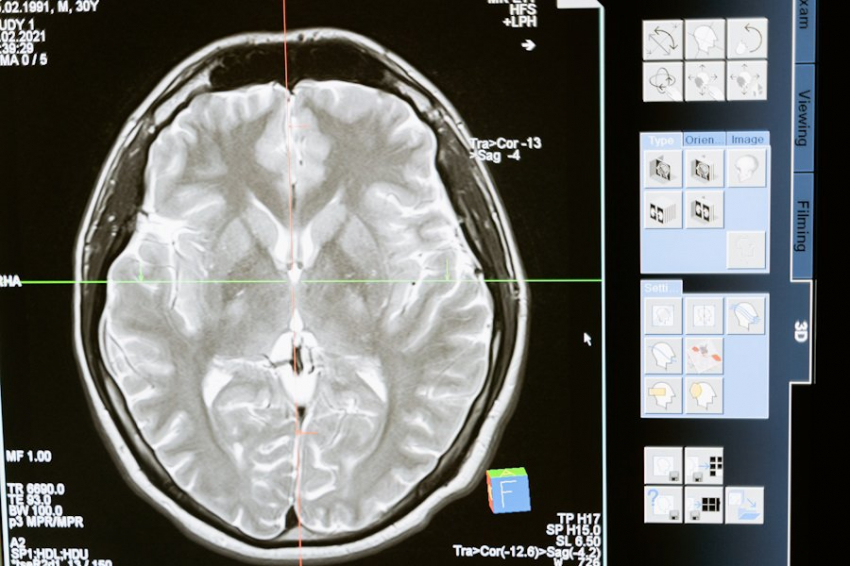

Переутомление возникает, когда ваш мозг находится в состоянии гипервозбуждения, что мешает естественному процессу засыпания. В течение дня в мозге накапливаются нейрохимические вещества, такие как аденозин, которые создают давление сна. Однако при переутомлении мозг становится слишком активным, что мешает этому процессу.

В состоянии повышенного возбуждения ваше тело не может перейти в сон. Это особенно влияет на голубое пятно в стволе мозга, которое должно замедлять свою активность для наступления сна. Если вы регулярно недосыпаете, ваш мозг становится ещё более подвержен тревожным мыслям, что затрудняет засыпание.